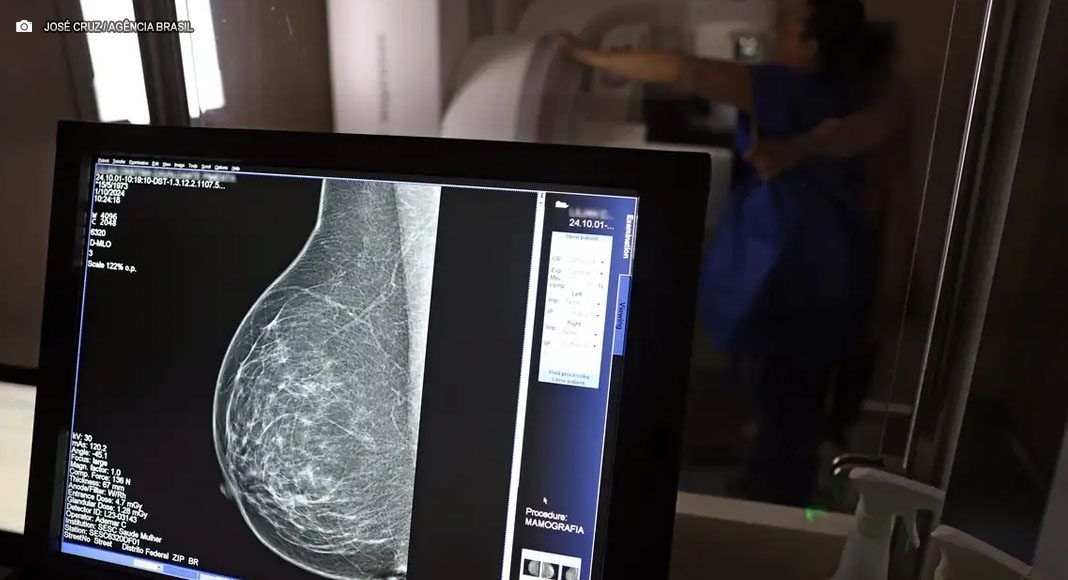

O Ministério da Saúde (MS) alterou a recomendação para mamografia no Sistema Único de Saúde (SUS), passando a orientar o exame para mulheres a partir dos 40 anos, mesmo sem sintomas. A medida, anunciada nesta terça-feira (23), visa intensificar a detecção precoce do câncer de mama, doença que concentra 23% dos casos em mulheres de 40 a 49 anos, o que aumenta as chances de cura. Até então, a mamografia de rotina na rede pública era indicada somente a partir dos 50 anos.

A pasta informou que a nova recomendação é feita sob demanda e em conjunto com um profissional de saúde, para que a paciente seja orientada sobre os benefícios e desvantagens do rastreamento. De acordo com o ministério, 30% das mamografias feitas pelo SUS já ocorrem em mulheres com menos de 50 anos, o equivalente a mais de 1 milhão de exames apenas em 2024.

O Ministério da Saúde também ampliou a idade máxima para o rastreamento ativo, que passa de 69 para 74 anos. A decisão é baseada em dados que mostram que quase 60% dos casos da doença estão na faixa etária de 50 a 74 anos. A medida, segundo o órgão, aproxima o Brasil das práticas internacionais adotadas em países como a Austrália, fortalecendo o compromisso do governo com o diagnóstico precoce e o cuidado integral à saúde da mulher.